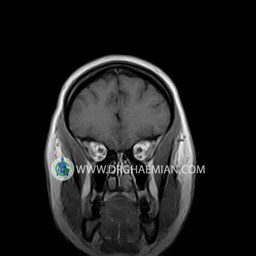

پزشکان اغلب از تصویربرداری ام آر آی برای تشخیص و درمان عارضه های پزشکی که فقط با استفاده از اشعه ایکس یا میدان مغناطیسی و امواج رادیویی قابل مشاهده است، استفاده می کنند. دستگاه ام آر آی تصاویر دقیق از ساختار های داخلی بدن ایجاد می کند. در این کیس نوریت اوربیت چب و سلای خالی بیمار مشاهده می شود.

ORBIT MRI

(with and without contrast)

Technique:Axial T1 , Axial , sagittal , coronal FSE T2 , coronal T1, sagittal fat sat T2 , Axial , sagittal T1 post Gd .

The both orbit are symmetrical and of normal size , with normal development of the orbital cones .

The bony orbital walls show a normal configuration with smooth and, sharp margins .

No foci of bone destruction , no circumscribed expansion of the bony or soft – tissue components of the orbital are evident .

The globes are symmetrical and of normal size and the ocular contents show normal signal characteristics .

The ocular walls are smooth , sharply defined , and of normal thickness .

The retrobulbar fat, ophthalmic vein and lacrimal apparatus are unremarkable .

Evaluable portions of the neurocranium and paranasal sinuses show no abnormalities .

No seen any evidence of ocular herniation

– Small fluid around the left optic nerve with mild edema suggestive for left optic neuritis

– Extension of suprasella cistern to sella with thin pituitary gland in floor of sella ( empty sella )

are seen

REPORTED BY :Dr DrNaser. Ghaemian.